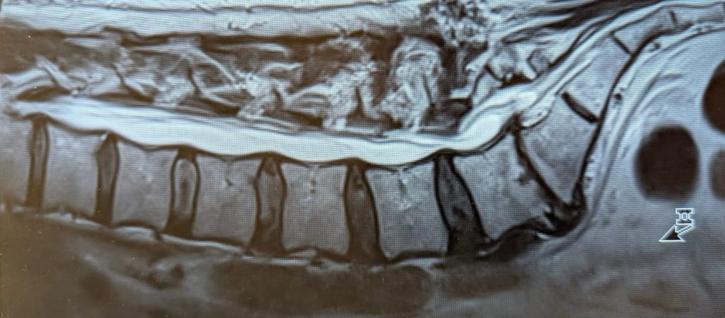

Ich bin ja seit 20 Jahren Rückenpatient und hatte bereits drei Operationen an der Wirbelsäule. Um hier nicht gleich alles festschrauben zu müssen, haben wir eine Therapie mit PRT-Spritzen und Physiotherapie gemacht. Dies und leider jede Menge Medikamente sorgten dafür, dass ich auf einem erträglichen Schmerzlevel blieb. Einzig die Neuropathien, ausgelöst durch einen dauerhaft gequetschten Nerv, blieben mir. Aber die waren ein Feind, an den ich mich gewöhnen konnte.

Aber das viele unbequeme Sitzen ließ dann den letzten Rest Gewebe zwischen den Wirbeln L5 und S1 verschwinden und das löste dann den Super-GAU aus: Im August einen 100-Meiler gelaufen, im September einen Marathon gelaufen, im Oktober an Krücken gelaufen. 😮